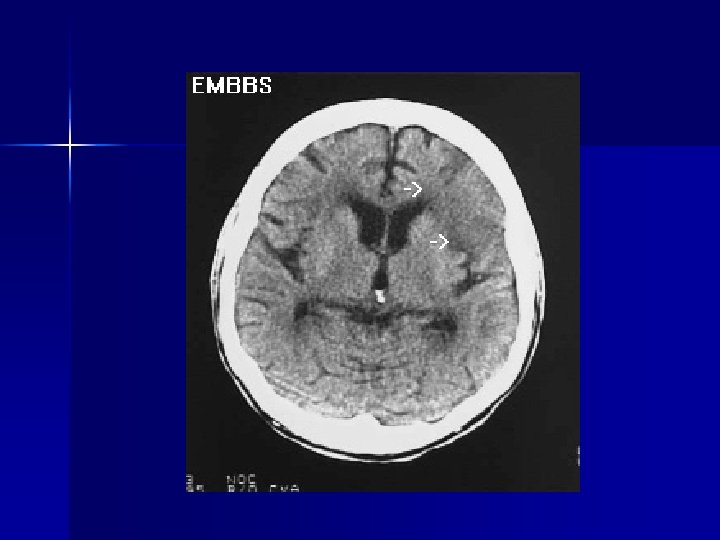

Subarachnoid Hemorrhage n n n n 1/10, 000 in U. S. Young, median age 50 50% mortality at 6 months 50% with initially normal exam, vitals, absence of neck stiffness Caused by anneurysm or AVM rupture Diagnosis: CT detects 93% in 24 hr, 80% after 24 hr Treatment: support ABCs, definitive treatment is coiling or clipping

Intraparenchymal Hemorrhage n n 55% report headache at onset of symptoms Suspicion if hypertension, known mass, bleeding diathesis, trauma Support ABCs REMO protocol Hypertensive Emergency if SBP>220, DBP>120 – EKG, IV, O 2, monitor – NTG, metoprolol for chest pain, pulm edema